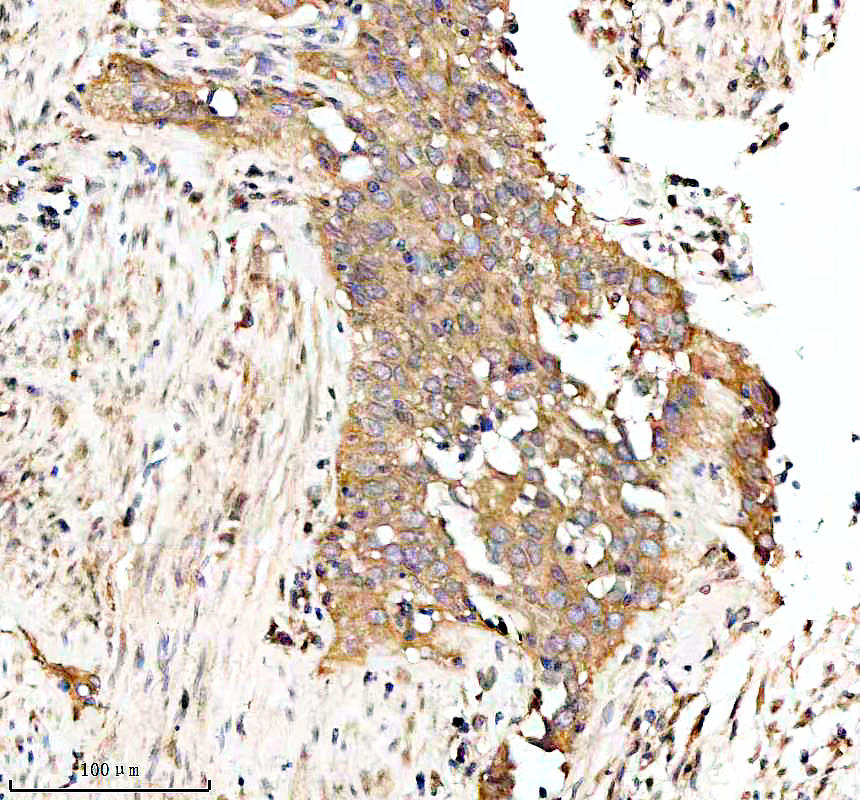

IHC analysis of BNIP3L using anti-BNIP3L antibody (BM5174) .

BNIP3L was detected in a paraffin-embedded section of human liver cancer tissue. The tissue section was incubated with rabbit anti-BNIP3L Antibody (BM5174) at a dilution of 1:200 and developed using HRP Conjugated Rabbit IgG Super Vision Assay Kit (Catalog # SV0002) with DAB (Catalog # AR1027) as the chromogen.

IHC analysis of BNIP3L using anti-BNIP3L antibody (BM5174) .

BNIP3L was detected in a paraffin-embedded section of human liver cancer tissue. The tissue section was incubated with rabbit anti-BNIP3L Antibody (BM5174) at a dilution of 1:200 and developed using HRP Conjugated Rabbit IgG Super Vision Assay Kit (Catalog # SV0002) with DAB (Catalog # AR1027) as the chromogen.